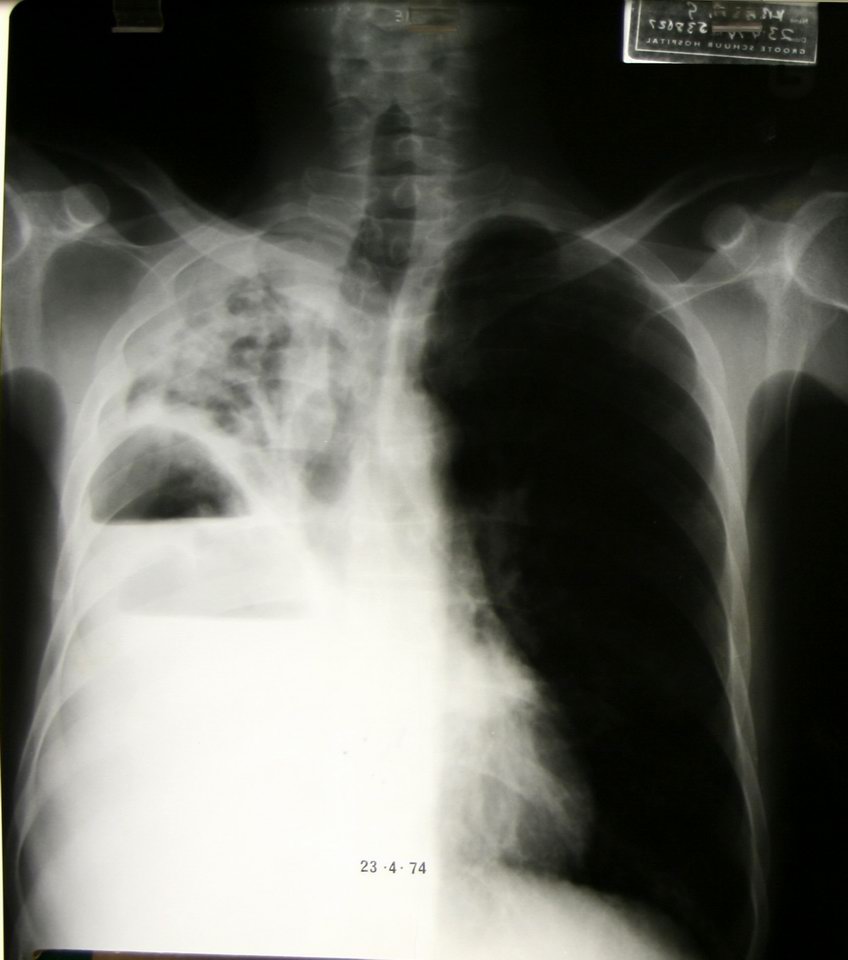

This patient has both a pulmonary abscess and an empyema at the same time! |

Lateral view, same patient |